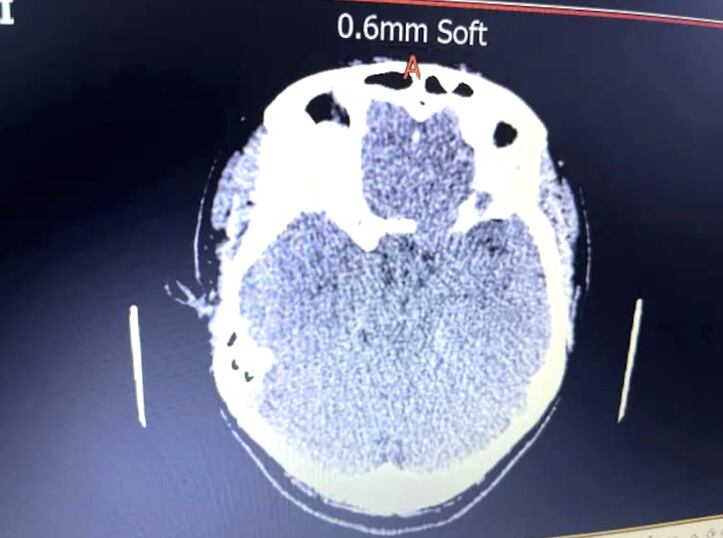

Por ese motivo, solicitó otra cita con la misma médica, quien le realizó una resonancia magnética. ¿El resultado? Devastador. Encontraron un tumor del tamaño de una pelota de tenis que empujaba el ojo hacia adelante. Le dijeron que debía pasar por una cirugía de urgencia.

“Estaba devastada y llorando por la noticia. En mi mente pensaba cómo se lo iba a decir a mis dos hijos. Los médicos me dijeron que mi tumor era complejo y, aunque estaba detrás de mi ojo, apenas tocaba mi nervio óptico, razón por la cual todavía tenía vista. Pasó desde la parte superior de mi cabeza, debajo de mi ojo y fue creciendo en mi cráneo”, reveló.

Cuando le hicieron otros estudios, finalmente le confirmaron que tenía un meningioma intraóseo. Tras la noticia, pasó por una operación de 10 horas y regresó a trabajar en marzo de 2023.